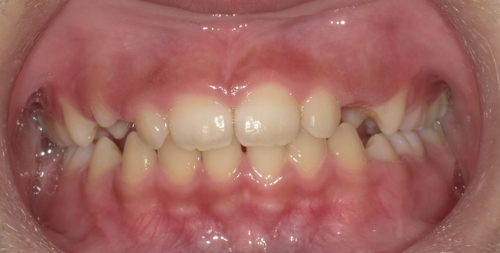

タイプⅢは受け口や交叉咬合に使います。大人の場合は顎の成長が止まっているので、反対咬合・受け口の場合は歯の軸を変えて治す場合と遺伝的に下顎そのものが大きい場合は外科手術で下顎の骨を切って治す場合があります。小児の場合は、まだ下顎の成長が始まっていないので、できるだけ上顎を積極的に成長させなければなりません。受け口・反対咬合だと、下の前歯が上の前歯の前にあるので、上の顎が前方に成長するのを妨げてしまうので、受け口だったら出来るだけ早くに改善する必要があります。下の写真のように短期で改善することが出来ます。

↓

最初から8カ月で受け口は改善していますし、さらに歯と歯の間に隙間が生じているので歯列が拡大しているのが分かります。